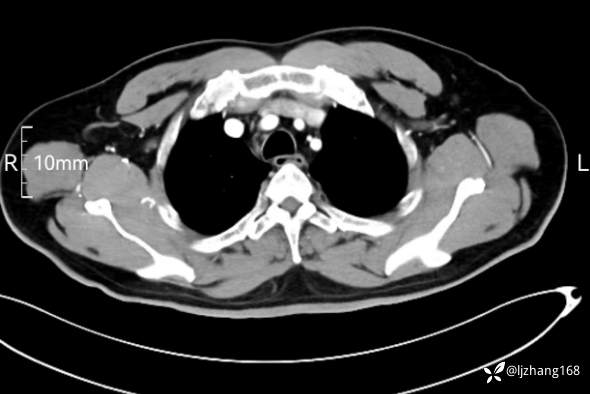

辅助检查:糖化血红蛋白12.3%。肺炎支原体IgG、IgM、呼吸道合胞病毒均未见明显异常。胸部CT:右肺上叶阻塞性肺炎。